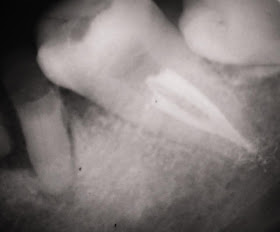

Caso Clínico da Profa. Andressa Pais - Equipe de Endodontia de Campinas / Extensão Vila Velha-ES

Sistema rotatório Protaper

PUI - passive ultrasonic irrigation

Obturação com Onda Contína de Condensação + AHPlus